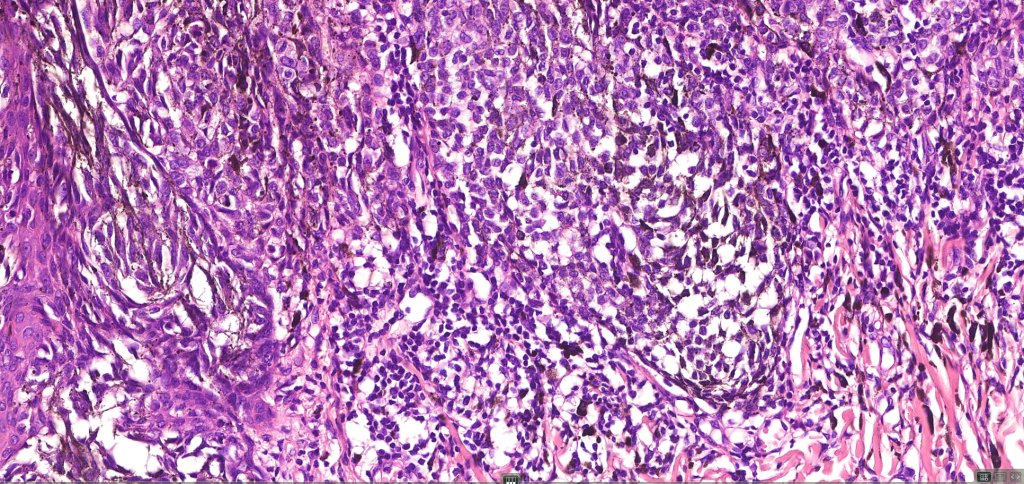

•Central focal Pagetoid spread & elimination of nests sometimes seen

•Junctional mitoses

•Adnexal involvement

. Lymphocytic infiltrate often seen at base